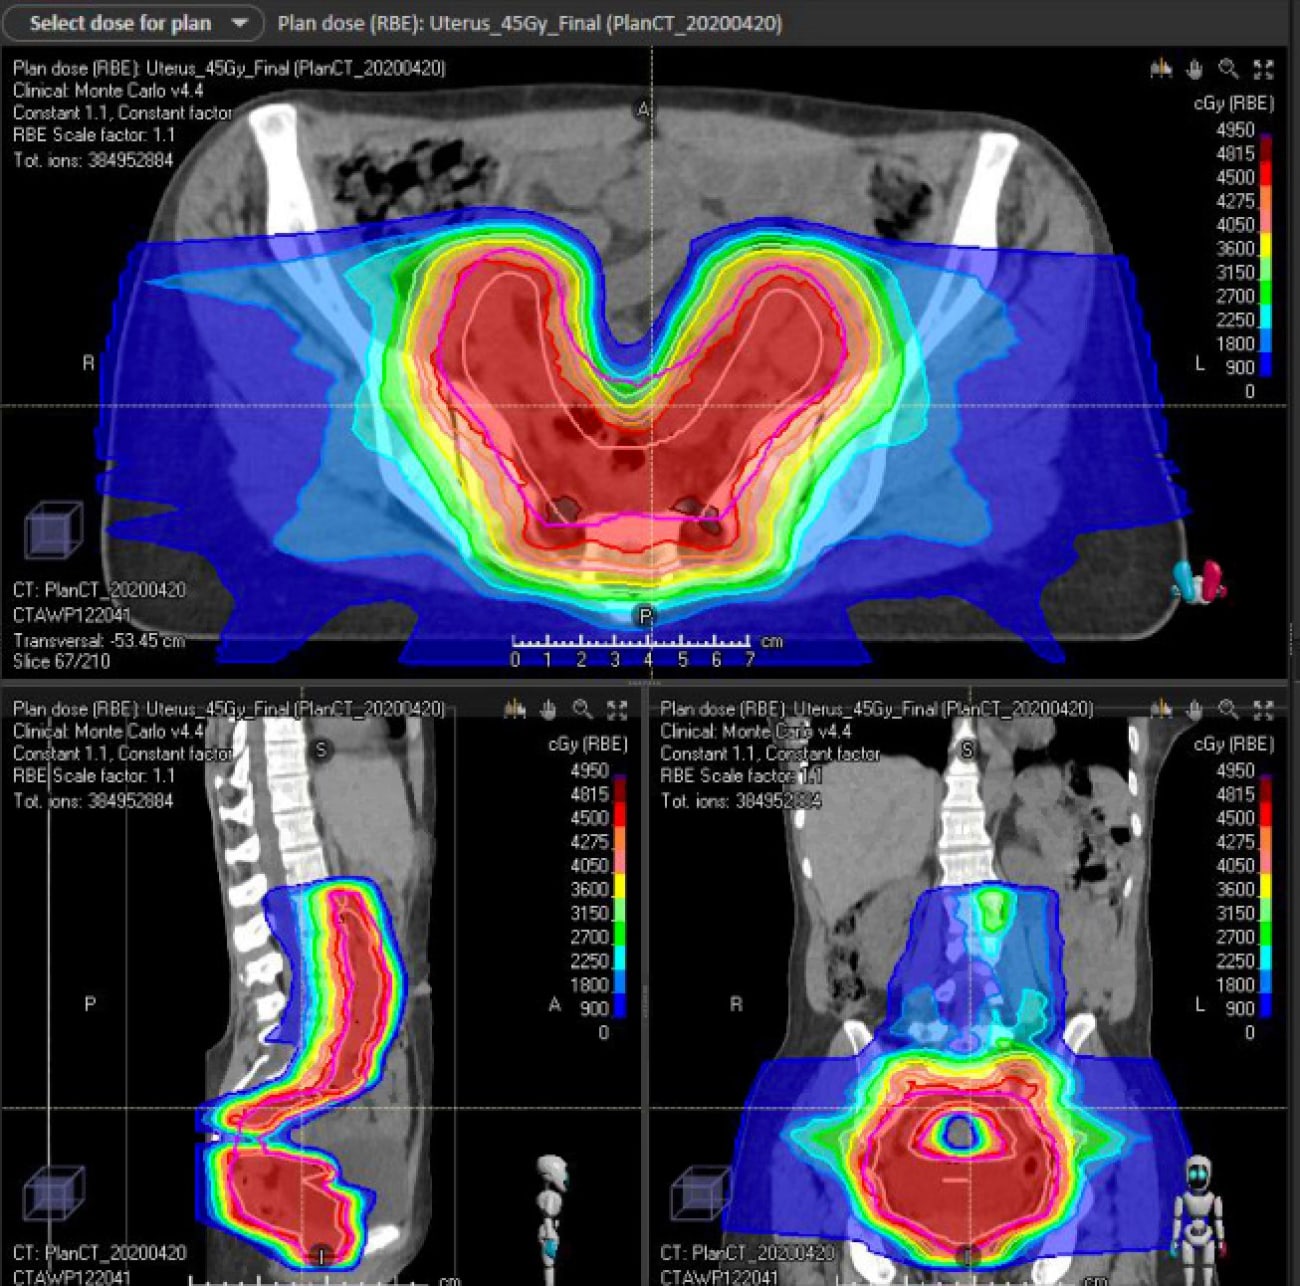

Case 1| UTERINE CARCINOSARCOMA WITH EXTENDED FIELDS TO PARA-AORTIC NODES

Patient is a 60-year-old woman with postmenopausal woman with a history of FIGO stage IIIC1 (grade 3 carcinosarcoma of the uterus, 75% myometrial invasion (MMI), no lymphovsacular space invasion (LVSI), 2/2 lymph nodes involved. She was treated with total abdominal hysterectomy and bilateral salpingo-oopherectomy with pelvic lymph node dissection and 6 cycles of adjuvant Carbo/Taxol.

Treatment: Given her high grade and aggressive histology, decision was made to use the extended field to cover para-aortic nodes. She was treated with 55 Gy (45 Gy pelvis + 10 Gy boost)